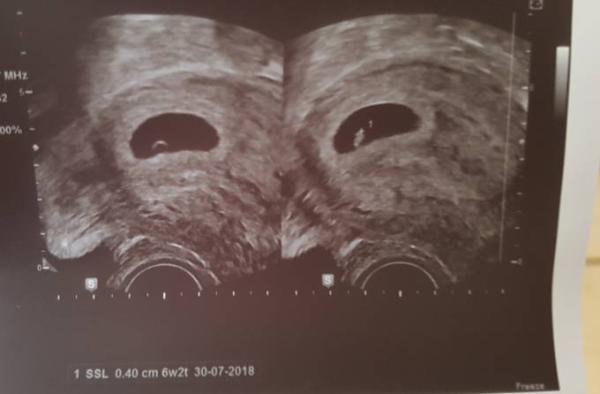

Komme grade vom Arzt. Es ist alles prima und man hat das Herz schlagen sehen

Oh wie toll! Das sieht ja gut aus.

Süß dein Bildchen. So sah mein erstes auch etwa aus.